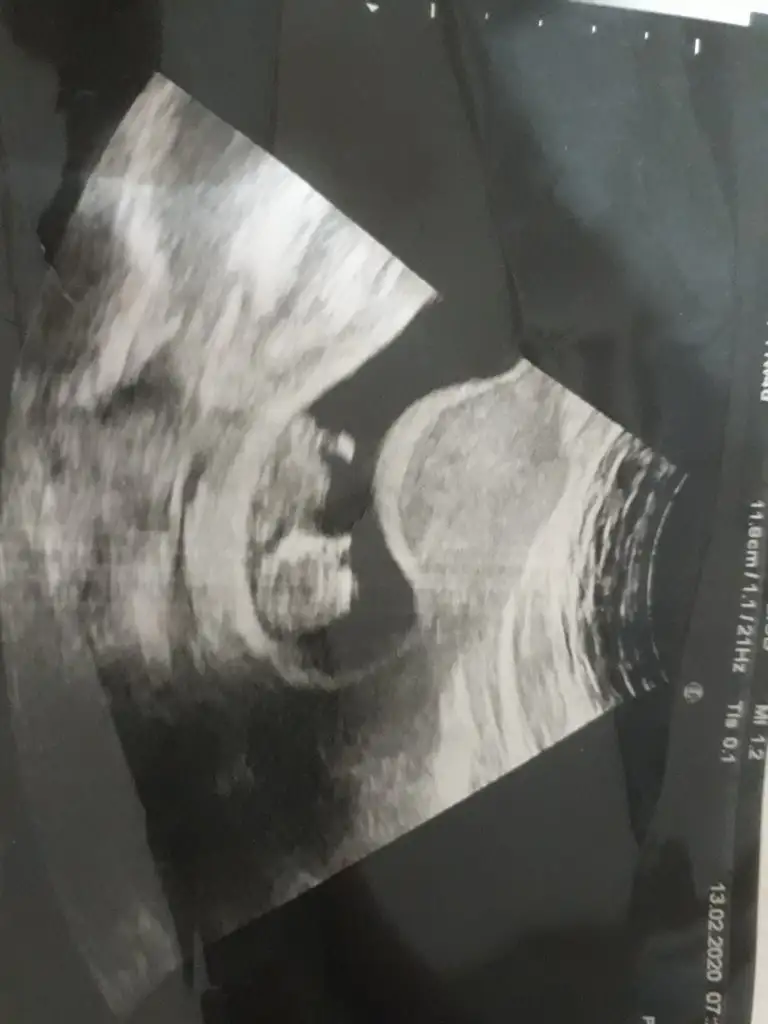

Emin olmamakla birlikte sanki kız nub tarafı çok karanlık başka usg varmı paylaşınEki Görüntüle 2590346 Eki Görüntüle 2590346 Çok belirgin değil ama 12.hafta usg mizIkra meyra Eki Görüntüle 2590346

10+4 te ki vardı ona da kız demiştinizEmin olmamakla birlikte sanki kız nub tarafı çok karanlık başka usg varmı paylaşın